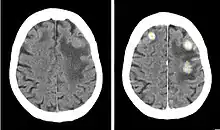

Iopentol (trade name Imagopaque) is a pharmaceutical drug that was used as a radiocontrast agent for X-ray imaging in Europe.[1]

Uses included arteriography (imaging of arteries), venography (imaging of the veins) and CT scan enhancement, urography (imaging of the urinary system), arthrography (imaging of the joints), endoscopic retrograde cholangiopancreatography (ERCP; imaging of bile and pancreatic duct), hysterosalpingography (imaging of the uterus and fallopian tubes), and gastrointestinal studies.[1]

Iopentol is an iodine-containing, water-soluble radiocontrast agent. The iodine atoms readily absorb X-rays, resulting in a higher contrast of X-ray images. It has a low osmolality, meaning that the solution has a relatively low concentration of molecules; this is usually associated with fewer adverse effects than high-osmolality contrast agents.[1][2]